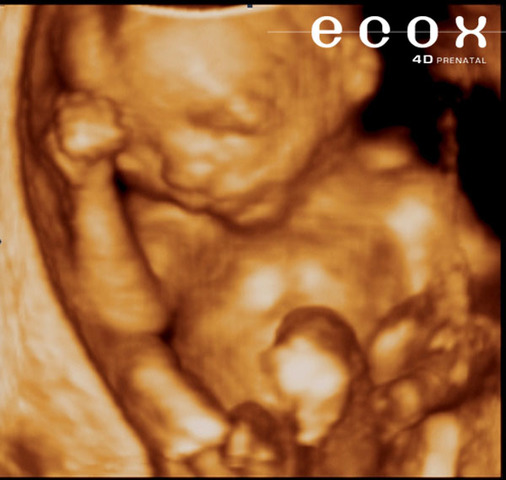

• SEMANA 8

SEMANA 8

Los rasgos faciales del embrión ya son más evidentes: se forman la nariz y el labio superior, las orejas empiezan a tomar su forma y los ojos se cubren con la piel que formará los párpados,se forma la piel, el corazón posee ya cuatro cámaras, se diferencian las válvulas aórtica y pulmonar,

• SEMANA 9 (FIN DE LA ETAPA EMBRIONARIA)

SEMANA 9 (FIN DE LA ETAPA EMBRIONARIA)

Aparecen las manos con todos sus dedos, las piernas se alargan, aparecen los pies con todos sus dedos, primero las muñecas y después los tobillos,la cabeza ya no está tan desproporcionada y el cuerpo empieza a alargarse, la cara va tomando una forma más normal: los ojos migran a la parte frontal, se forman los párpados y la boca ya puede incluso abrirse,los huesos siguen su crecimiento, la cola embrionaria del final de la columna vertebral desaparece,se forma el tubérculo genital